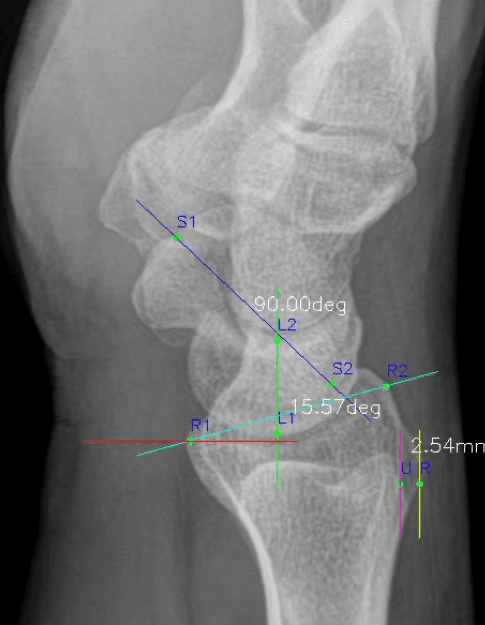

WALK101, Wrist_Lat_AIX 출시… 손목 X-ray(LAT) 자동 측정으로 임상 파이프라인 확장

Wrist_Lat_AIX는 손목 Lateral X-ray에서 주요 불안정 진단 관련 지표를 자동 측정하는 AI 솔루션으로, MFDS 1등급 의료기기 인증을 획득했습니다.

#Wrist_Lat_AIX#MFDS#Class 1